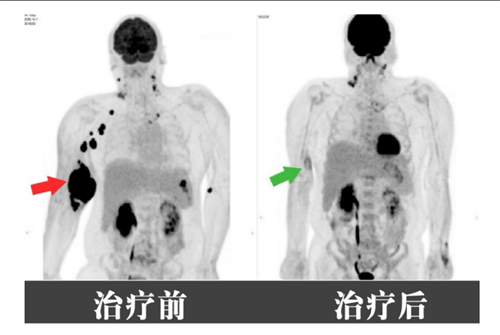

血液内科主任尹亚飞带领团队针对患者的病情迅速制定治疗方案:先降低肿瘤负荷,再衔接化疗。经过六次R-DA-EPOCH方案治疗,刘兴南右侧手臂肿瘤完全消失,成功保住了手臂。目前他已出院回归正常生活,定期复查巩固疗效。